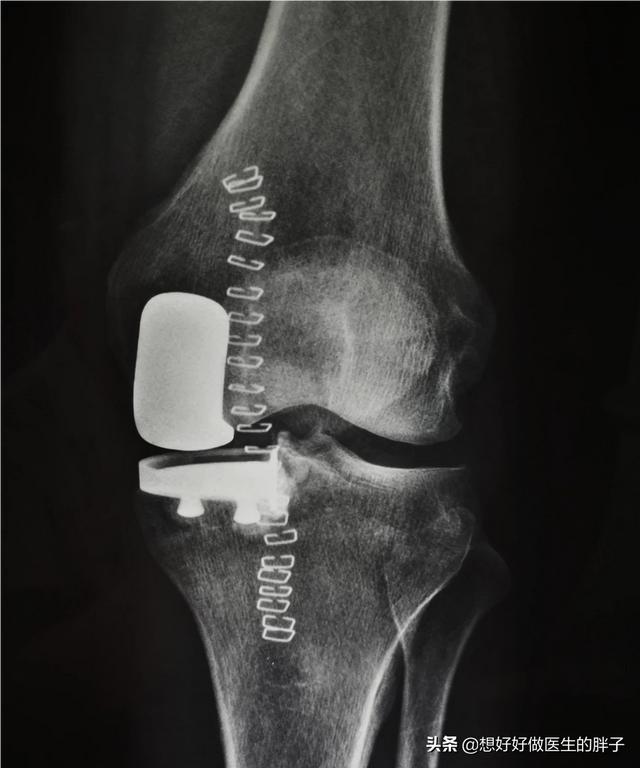

進行期通常、膝の痛みとして現れ、関節の屈曲や伸展に著しい障害をきたす患者もいる。安静時痛と夜間痛それは、患者の状態が、それを解決するために手術が必要な段階にまで達していることを示すサインである。このような手術を私たちは人工膝関節置換術人工膝関節置換術は、膝関節の骨を全部抜いて人工関節に置き換える手術だと思っている人が多いようですが、それは間違いで、壊れた軟骨の表面を取り除き、金属の表面に置き換える手術なので、人工膝関節表面置換術ともいいます。また、現在の技術の進歩に伴い、患者さんの関節をより保護・保存するために、以下のような手術も行われるようになりました。部分関節形成術。

人工関節置換術の外科的治療を受ける場合、体系的なリハビリテーションをしっかり行えば、術後の成績は非常に良くなる。